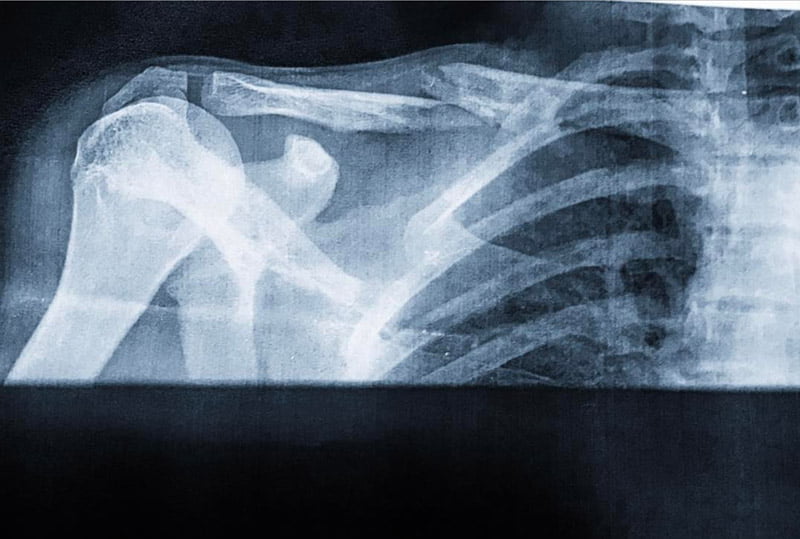

Malheureusement, le pilote italien a sévèrement chuté en fin de deuxième journée et s’est relevé avec une clavicule droite fracturée. Après avoir subi divers contrôles médicaux à l’hôpital de Valence, il sera décidé s’il doit retourner en Italie pour y subir l’acte chirurgical afin de réduire cette fracture.